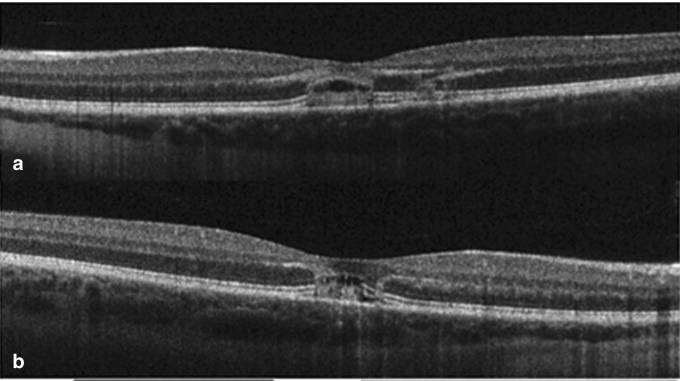

In der Makula zeigt sich eine gelbliche Läsion, die OCT-Aufnahme offenbart das "Loch" wie unten dargestellt:

Nach 2 Monaten erholte sich die Sehschärfe auf 0,67, nach 19 Monaten schließlich auf 1,0. Allerdings war die Makulaempfindlichkeit des linken Auges herabgesetzt, und das "Loch" blieb bestehen.

Nach 8 Wochen sank die Sehschärfe des rechten Auges auf 0,5 und die des linken Auges auf 0,4. Der Augenhintergrund zeigte folgende Befunde, mit Diskontinuitäten in der ellipsoiden Zone der Photorezeptoren und der äußeren Grenzmembran.

Nach 12 Monaten erholte sich die Sehschärfe beider Augen auf 0,67. Dennoch blieb die Makulaempfindlichkeit beider Augen herabgesetzt, und die "Löcher" in der Makula waren weiterhin sichtbar.